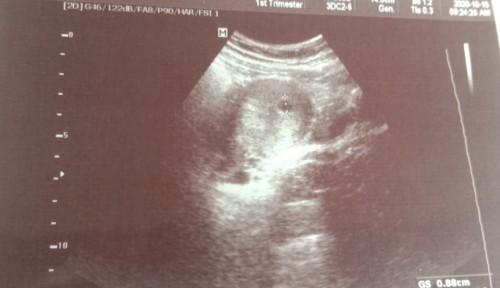

ini saya waktu usg 6w bund baru kantong ny aja yg keliatan

bun mau tanya, perkiraan kan ini 6 minggu, masih kantong belum ada titik putih, apakah memang di usia segini belum muncul? mohon infonyaaaa ??